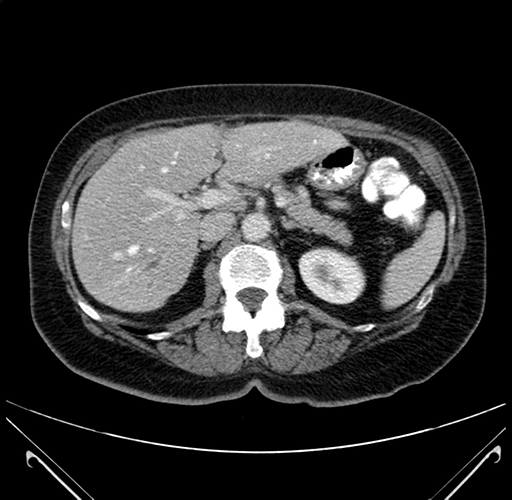

Pre-Chemo: Axial Venous

Axial Venous

Imaging analysis

Based on your CT findings, which issue(s) would give reason for "planned slowing down moment(s)" in this case?

Considering a standard right hepatectomy procedure, what step(s) of the operation would you do differently in this case?